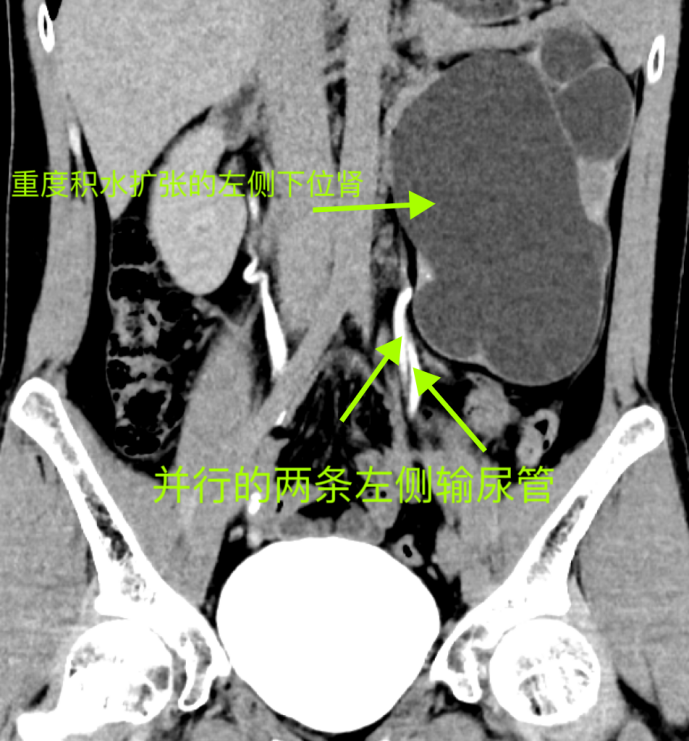

在聽完岳峰主任詳盡的解釋后,陳先生迅速辦理了入院手續(xù),并進一步完善了泌尿系CTU及腎CTA+CTV檢查。檢查結(jié)果果然顯示,陳先生左側(cè)存在重復(fù)腎及重復(fù)輸尿管,并且更為罕見的是下位重復(fù)腎伴有重度擴張積水。

術(shù)前腎CTA+CTV影像

術(shù)前CTU冠狀位影像